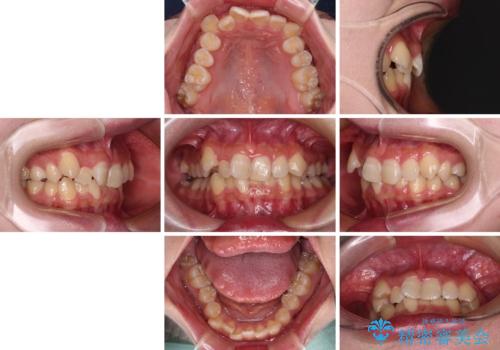

- 上下の八重歯を気にして来院された患者様です。

非抜歯矯正で歯列を整えると、治療後に口元が今よりも突出する可能性が高かったため、上下左右の小臼歯4本を抜歯し、ワイヤー装置にて矯正治療を行うこととしました。

右上の八重歯の影響で、右側は上顎歯列が前方位の咬み合わせとなってしまっていたため、上顎は第一小臼歯を、下顎は第二小臼歯を抜歯することで咬み合わせや上下正中を調整することとしました。